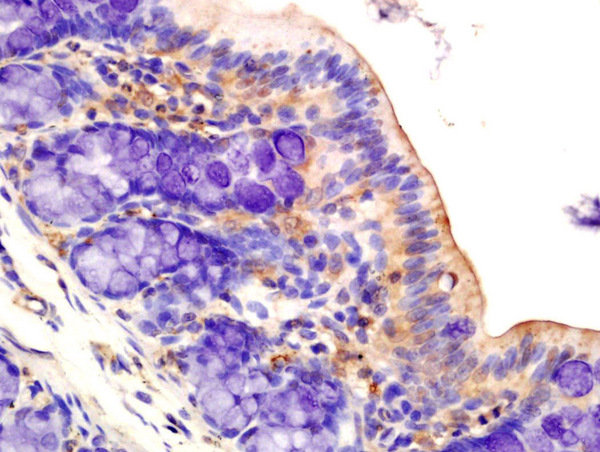

Paraformaldehyde-fixed, paraffin embedded mouse brain; Antigen retrieval by boiling in sodium citrate buffer (pH6) for 15min; Block endogenous peroxidase by 3% hydrogen peroxide for 30 minutes; Blocking buffer (normal goat serum) at 37°C for 20min; Antibody incubation with AMPK alpha-1 Polyclonal Antibody, Unconjugated (bs-10344R) at 1:400 overnight at 4°C, followed by a conjugated secondary and DAB staining.

- Applications SupplierWB(1:300-5000), ELISA(1:500-1000), FCM(1:20-100), IHC-P(1:200-400)